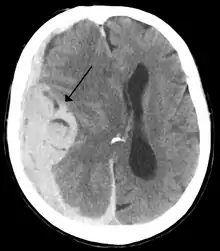

Midline shift

Midline shift is a shift of the brain past its center line.[1] The sign may be evident on neuroimaging such as CT scanning.[1] The sign is considered ominous because it is commonly associated with a distortion of the brain stem that can cause serious dysfunction evidenced by abnormal posturing and failure of the pupils to constrict in response to light.[1] Midline shift is often associated with high intracranial pressure (ICP), which can be deadly.[1] In fact, midline shift is a measure of ICP; presence of the former is an indication of the latter.[2] Presence of midline shift is an indication for neurosurgeons to take measures to monitor and control ICP.[1] Immediate surgery may be indicated when there is a midline shift of over 5 mm.[3][4] The sign can be caused by conditions including traumatic brain injury,[1] stroke, hematoma, or birth deformity that leads to a raised intracranial pressure.

Doctors detect midline shift using a variety of methods. The most prominent measurement is done by a computed tomography (CT) scan and the CT Gold Standard is the standardized operating procedure for detecting MLS.[5] Since the midline shift is often easily visible with a CT scan, the high precision of Magnetic Resonance Imaging (MRI) is not necessary, but can be used with equally adequate results.[5] Newer methods such as bedside sonography can be used with neurocritical patients who cannot undergo some scans due to their dependence on ventilators or other care apparatuses.[6] Sonography has proven satisfactory in the measurement of MLS, but is not expected to replace CT or MRI.[6] Automated measurement algorithms are used for exact recognition and precision in measurements from an initial CT scan.[7] A major benefit to using the automated recognition tools includes being able to measure even the most deformed brains because the method doesn’t depend on normal brain symmetry.[7] Also, it lessens the chance of human error by detecting MLS from an entire image set compared to selecting the single most important slice, which allows the computer to do the work that was once manually done.[7]